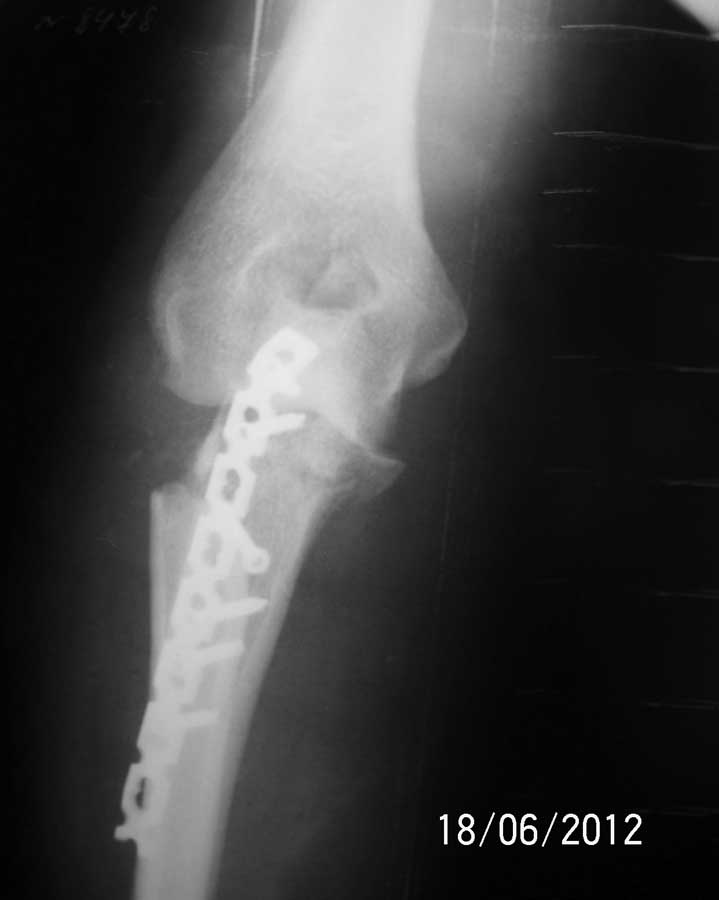

Доброго времени суток коллеги.

Операция состоялась. Выполнить остеосинтез головки лучевой кости не удалось из-за оскольчатого характера перелома. Её пришлось резецировать. Произведен остеосинтез проксимального отдела локтевой кости LCP реконструктивной пластиной.

Рентгенограммы прилагаются.

Молодцы. В боковой проекции смотрится не плохо, а почему не стали блокировать проксимальные отверстия в пластине.